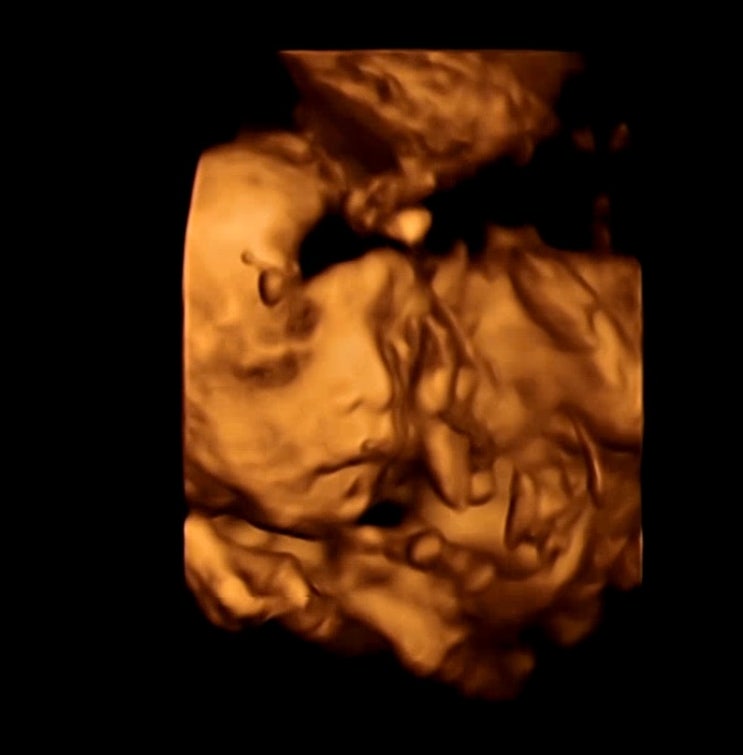

벌써 32주가 되었어요! 서면 셀프스튜디오에서 만삭 촬영을 셀프로 했어요! 촬영 장소는 우리 스튜디오입니...